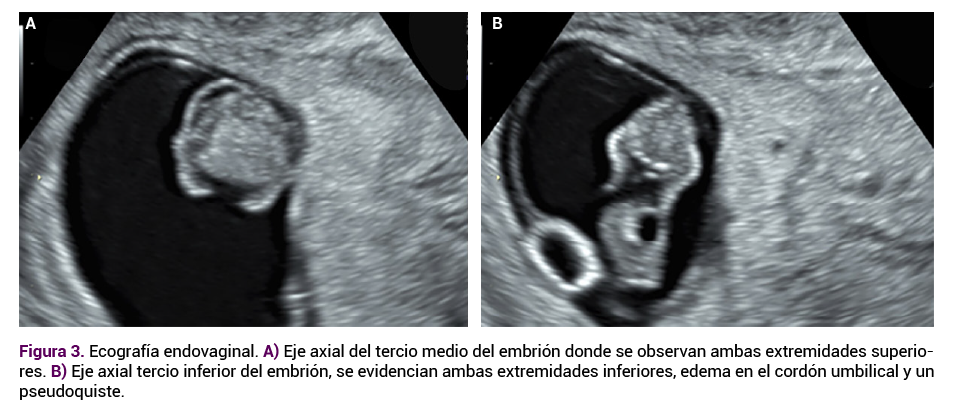

Acudió a consulta a las 9 semanas de embarazo para seguimiento. El ultrasonido del primer trimestre, con equipo de alta definición Voluson P8, reportó útero en anteverso-flexión, miometrio homogéneo y bordes regulares. En su interior, en localización fúndica, se observó saco gestacional de bordes regulares con un embrión de 24.1 mm de longitud craneocaudal (9.1 semanas) y frecuencia cardiaca de 175 latidos por minuto (Figura 1 A y B), con malformación craneal.

<strong>Figura 1</strong>

Figura 1. Embrión de 9.1 semanas con frecuencia cardiaca registrada y alteraciones craneofaciales iniciales (vistas A y B).